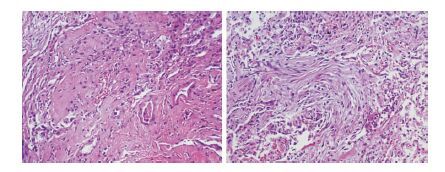

患者入急诊时已明显呼吸窘迫,血氧饱和度进行性下降,立刻行气管插管机械通气,呼吸机参数:SIMV+PSV模式,f 22次/min,PC 20 cmH2O(1 cmH2O=0.098 kPa),PEEP 15 cmH2O,FiO2 100%。但患者血氧饱和度仍进行性下降,血气分析:PaO2 45 mmHg,OI 45 mmHg;即转送ICU行V-V ECMO支持,患者血氧饱和度逐渐上升,生命体征逐渐稳定。因高度怀疑禽流感病毒感染,立即启用应对重症禽流感病毒方案:抗病毒(奥司他韦 150 mg Q12 h,空肠管注入);抗细菌(美罗培南 1.0 Q8 h,莫西沙星 250 mL,QD);输注甲强龙注射液(80 mg,QD)和丙种球蛋白。按以上方案治疗一周后病情有好转,OI最高上升至 102 mmHg,胸片渗出影也逐渐吸收,痰液中病毒拷贝数下降。但第8天后患者开始发热,查PCT 23.32 ng/mL,WBC 15.77×109 L-1,并在痰培养出多重耐药鲍曼不动杆菌,抗生素调整为:替加环素、米诺环素、舒普深、卡泊芬净,但病情无明显好转,体温、白细胞和PCT进行性上升,感染加重,最后出现多器官功能衰竭,于入院后第23天抢救无效死亡。住院23天的临床指标变化见表 1,病毒拷贝数见表 2,死亡后取得肺组织病理标本的结果见图 3。

| 肺泡塌陷,肺泡上皮轻度非典型增生,肺泡间隔大量纤维组织增生,伴淋巴细胞、中性粒细胞浸润,并见局灶含铁血黄素沉积,肺泡腔内见较多泡沫细胞。病变呈慢性炎伴部分肺实变改变。特殊染色:抗酸染色、六胺银、PAS均(-) 图 3 肺组织病理结果(右肺下叶,HE ×100) |

需要吸取教训包括:①患者入ICU早期因病情危重,病因未明,笔者选择了超广谱抗生素美罗培南,但这可能给细菌造成抗生素压力,筛选出耐药菌。回顾病例,该患者转入初期以病毒感染为主,应主要关注抗病毒治疗,抗细菌可先覆盖院外感染常见菌,不宜过早使用超广谱抗生素。②做好气道护理、院感控制、尽量减少侵入性操作、病情好转尽早撤下ECMO等措施,可能有助于延缓耐药菌出现,为抢救赢得时机。2013年报道的山东首例禽流感病例中[4],启动ECMO一周后能成功停机,虽然后期也出现泛耐药鲍曼不动杆菌感染,但使用替加环素和美罗培南后感染得到控制,这可能与停用ECMO的先决条件有关。本病例一周内虽有好转,但还未能达到脱机的条件,此时出现二重感染,治疗难度就显著加大了。③糖皮质激素使用的问题,回顾这两年来的禽流感病例,大部分使用激素,其理论依据是认为激素可以减轻全身炎症反应,减轻后期肺间质纤维化[5]。但已有研究显示在ARDS中使用激素未能降低病死率,反之有增加二重感染的风险。本病例也使用激素治疗,但从死亡后取得的病理结果看,患者肺间质纤维化非常严重,似乎未能看到激素在这方面的作用。上海报道的三例死亡病例[6],均有使用激素,其中一例早期虽成功拔管,但后期肺纤维化非常严重,第86天死于气胸。且激素有病毒复制持续性和二重感染的不良影响,因此激素的使用仍存在较大争议。钟南山指出:“近期的研究结果表明,不管是对HlNl或H7N9流感病毒感染的患者无针对性地使用糖皮质激素基本是无效的,甚至有害。但是对一些可能发展为ARDS的患者,选择恰当的时间窗及剂量给予糖皮质激素可能有益。这些均需要我们不断观察,不断总结”[7]。④从目前得到的证据,尽早使用神经氨酸抑制剂是值得推荐的,本病例使用药物过迟和不足量是应该吸取的另一个教训。⑤本病例病程监测病毒载量发现,病毒拷贝数在肠内给予神经氨酸抑制剂后逐渐下降,这说明经空肠管注入奥司他韦抗病毒治疗是有效的,且经空肠管注药的生物利用度要优于经胃管。因此,对于此类重症禽流感病例,应提倡尽早留置空肠管,尽早开始肠内足量给药,这可能是控制病毒复制的有效方法。